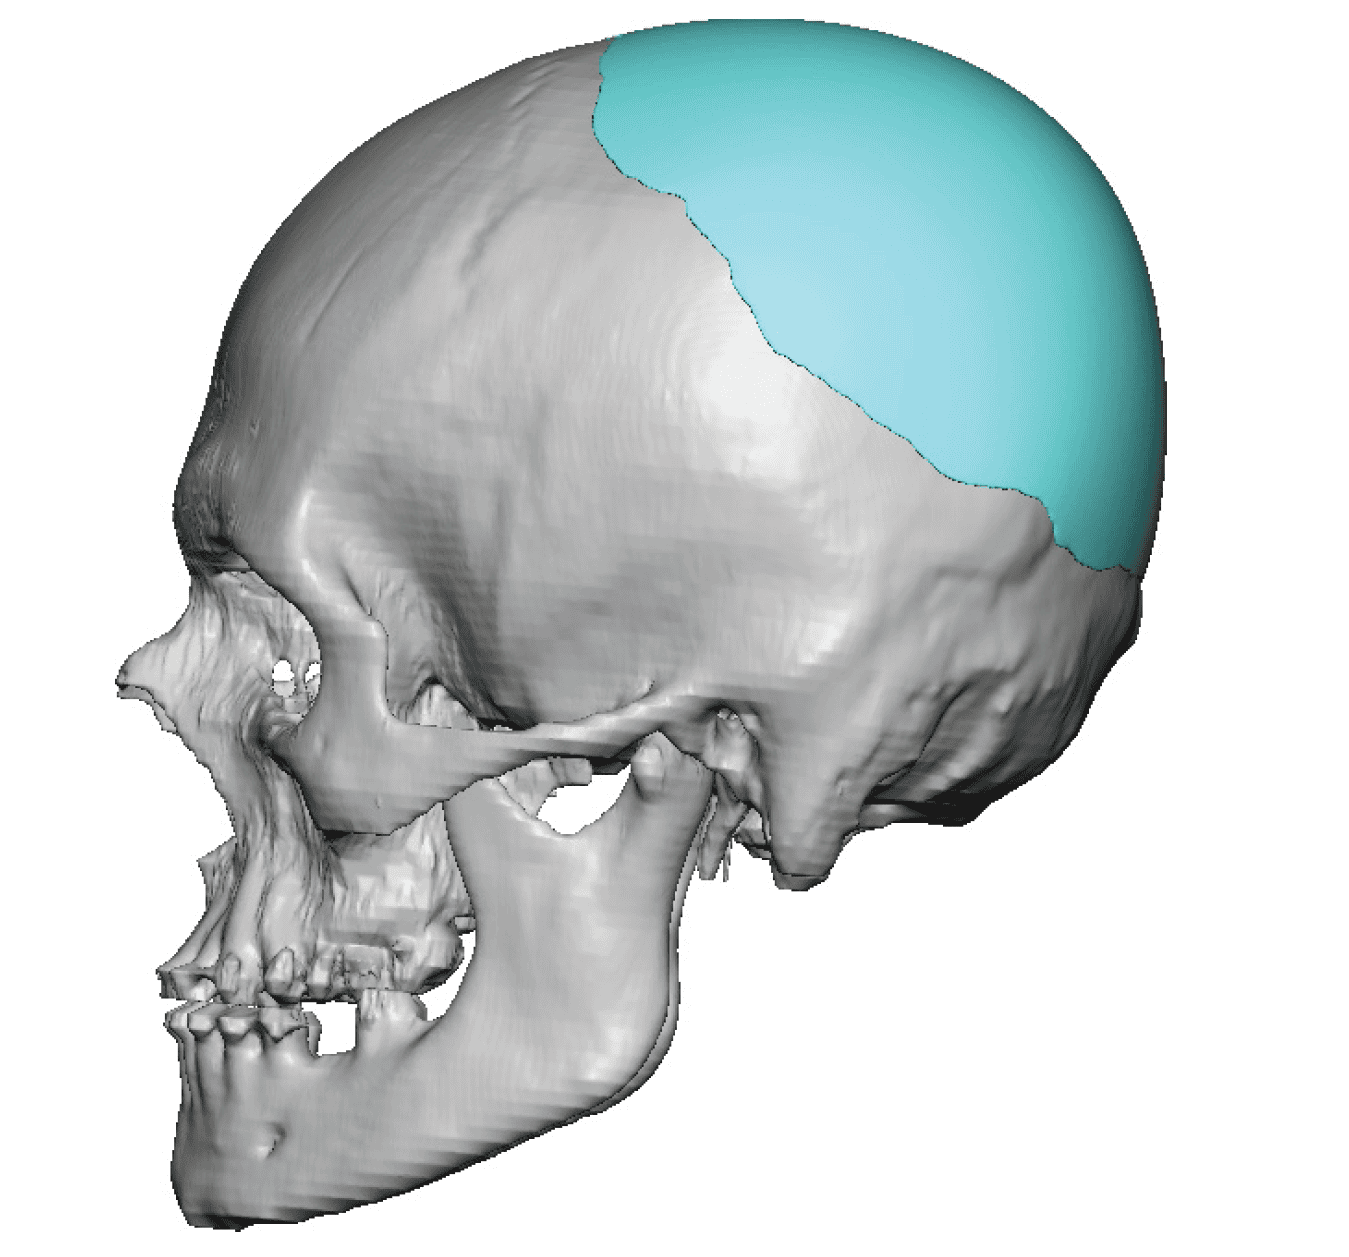

Patient 49

Desire for further skull augmentation after a primary skull implant.

Five years after an initial custom skull implant placement a new custom skull implant that increased the volume by 35% was placed.

Desire for further skull augmentation after a primary skull implant.

Five years after an initial custom skull implant placement a new custom skull implant that increased the volume by 35% was placed.